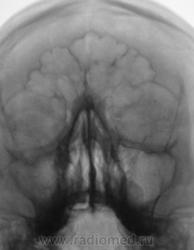

Пациент первый.

Киста, или что другое?

Больше похоже на кисту. Четкий округлый контур с характерным месторасположением. Хотя может и не так все просто)

да,  похоже на кисту, но справа снижена пневматизация верхнечел.пазухи за счет умеренного отека, я бы кисту слева под вопросом написала и направила на контроль

---------------------------------------------------------------------------------------------------------------------------------------------------------------------------------+1: как вариант,  можно предположить, что киста одонтогенного происхождения.